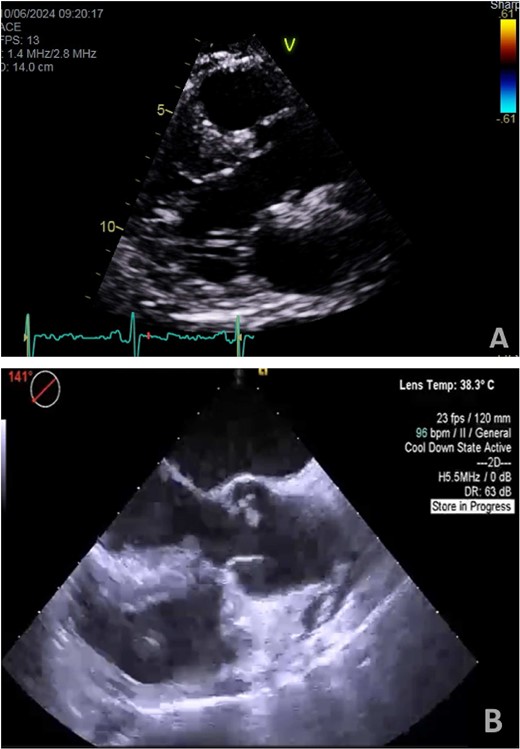

A 55-year-old man with hypertension and hyperlipidemia presented to our hospital with non-ST-segment myocardial infarction (NSTEMI). He was a smoker with no family history of heart disease. Patient was having class III angina for the previous 6 months but never sought medical help. He had no shortness of breath and no history of previous cerebrovascular accident (CVA). The patient underwent coronary angiogram that showed triple vessel disease with chronically occluded right coronary artery. Preoperative TTE showed left ventricular ejection fraction of 50% with mild mitral valve regurgitation and no aortic valve disease (Fig. 1A). Chest radiography was normal and his preoperative blood tests including C-reactive protein, Erythrocyte sedimentation rate (ESR), and complete blood count were normal. Blood cultures were negative. Patient underwent CABG during the same hospitalization due to his recurrent chest pain. Intraoperative TEE (Fig. 1B) showed a mass in the undersurface (ventricular side) of the non-coronary cusp (NCC) of aortic valve with normal valve function (tri leaflet valve). The differential diagnosis at that time included vegetation, calcification, or tumor. Median sternotomy was performed with ascending aorta and right atrial venous cannulation. CABG was performed with left internal mammary artery anastomosis to left anterior descending artery and reverse saphenous vein graft anastomosis to obtuse marginal artery. The aortic valve was exposed through transverse aortotomy and the mass was visualized in the ventricular side of NCC of aortic valve measuring 6 × 5 mm. It was white in color, rounded with some fronds (Fig. 2). The aortic valve was tri-leaflet valve with some calcifications noted in the other two cusps. The mass was then shaved off the valve and sent to histopathology. The leaflet was intact, and the aortic valve was tested and was normal with no regurgitation. Patient tolerated the procedure well and was weaned from cardiopulmonary bypass with small dose of Dobutamine. TEE at the end of operation showed well-functioning aortic valve with no aortic regurgitation. Patient was extubated 7 hours postoperatively and he had uncomplicated postoperative recovery and was discharged home 1 week postoperatively on dual antiplatelet therapy (Aspirin and Clopidegrol). Pathology report of the aortic mass (Fig. 3) showed 0.6 × 0.5 × 0.4 cm PFE (microscopic section showed multiple branching fronds and paucicellular avascular fibro elastic tissue lined by a single layer of endocardium). Patient remained well and asymptomatic at 3 months postoperatively.

(A) Preoperative transthoracic echo (Para sternal long axis view) showing clear aortic valve cusps with no mass. (B) Intraoperative transesophageal echo (midesophageal long-axis view at 140°–150°) showing mass attached to ventricular surface of NCC of aortic valve.